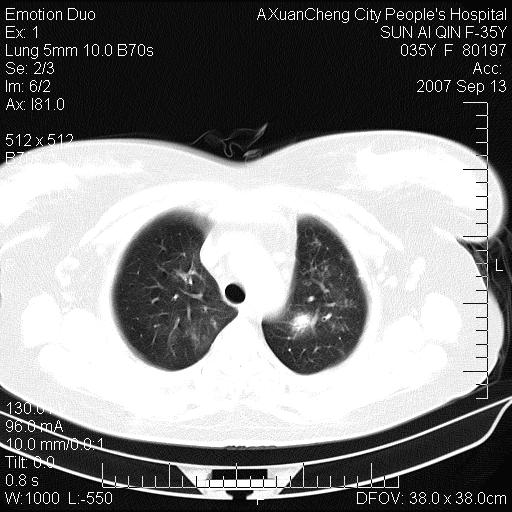

以下是引用天南地北在2007-9-13 13:43:00的发言:[br]考虑双肺、肺门侵润

以下是引用ydx_74在2007-9-13 15:42:00的发言:[br]仅看片,考虑右上肺癌并双肺转移,结合病史,考虑肺门、肺内淋巴侵润

以下是引用同在2007-9-13 15:08:00的发言:[br]支持肺门及双肺侵润.